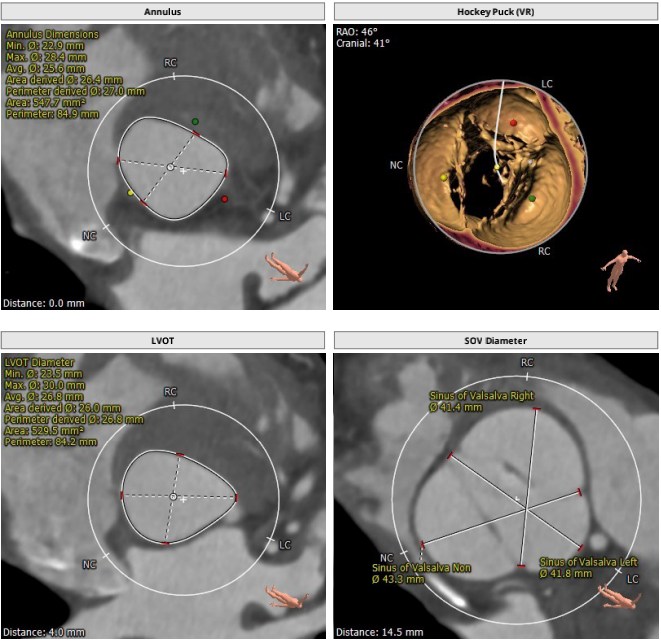

术前CT测量:

瓣环:27mm;LVOT:26.8mm;STJ:37.9mm;升主动脉:37.4mm;左冠高度:20.2mm;右冠高度:28.9mm;钙化积分:18mm3;瓣环与水平面夹角:29°;心尖入路夹角:108°。

计算机三维重建: